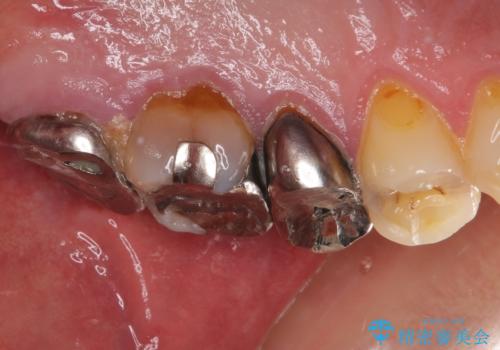

- 奥歯が痛いとのことで来院された患者様です。

歯肉に排膿の痕があり、叩いたり咬んだりすると痛みを感じていました。

根管治療を行い、その後フルジルコニアクラウンにて補綴することとしました。